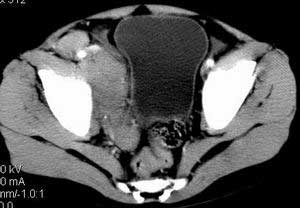

| 患者,男,9岁,因右下腹包块入院,血象不高,不规则发热,常超40度。 平扫: ![]() ![]() ![]() ![]() ![]() ![]() ![]() ![]() ![]() ![]() ![]() ![]() ![]() ![]() ![]() ![]() ![]() ![]() 增强: ![]() ![]() ![]() ![]() ![]() ![]() ![]() ![]() ![]() ![]() ![]() ![]() ![]() ![]() jiajie发言:骶椎右前区不规则软组织肿块,边缘光整,密度均匀,增强后均匀强化,右腹股沟区可见肿大淋巴结,临床有时发热,考虑淋巴瘤,儿童盆腔肿瘤应与神经母细胞瘤和横纹肌肉瘤鉴别。 longzhanghui发言:印象:盆腔右后壁不规则软组织肿块,并向前延伸.似为多个肿块融合,呈中等强化.初步考虑淋巴瘤. 听蝉观竹发言:右侧髂内、外组淋巴结肿大,从其形态和融合的情况看,同意大家意见-----考虑恶性病变,但是9岁男孩还要注意检查睾丸情况,有无隐睾? 常常类似情况是隐睾发生精原细胞瘤淋巴结转移,这个病例也要注意这一点!!! 广东凌发言:大家好,在这里我想说一下个人观点,我建议上传图片的同志能否辛苦一点就是把病史和图片都上传完整一点,比如这个病人的腹膜窗,并且这个病人的肠道的准备也是不怎么好,就从现有的质料看:病灶属于淋巴结肿大当无大的争议,有融合趋势,其内无坏死,边缘强化为主,故考虑:淋巴瘤!建议用腹膜窗看一下和肠道的关系! 阿圣发言:病灶属于淋巴结肿大当无大的争议,有融合趋势,其内无坏死,边缘强化为主,故考虑:淋巴瘤 结果是:淋巴瘤 病例来源:ct762。由宁静致远发布: http://www.radinet.com.cn/forum_view.asp?forum_id=4&view_id=2182 |